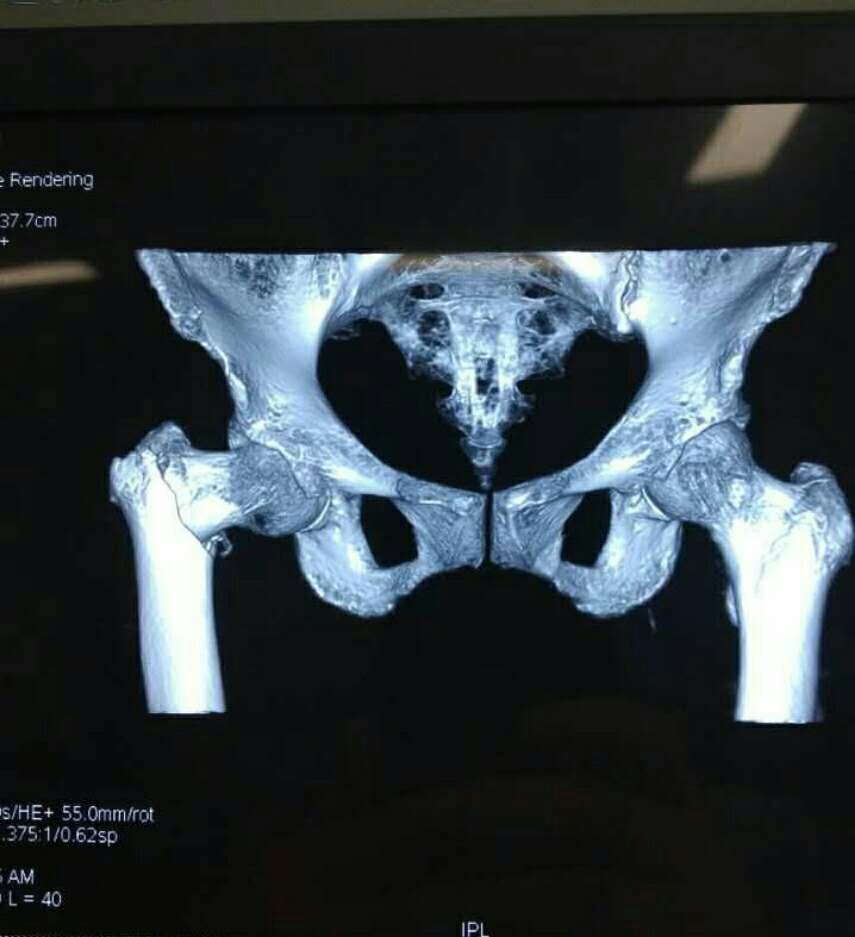

7月17日晚上,家住楚店镇周东村的王奶奶不慎在家摔倒,腿部剧烈疼痛,不能站立和行走,家人急忙将老人送至我院救治,经诊断为右股骨粗隆间骨折,需要住院治疗。副主任医师王洪灵为老人进行了详细的检查,发现患者不仅右股骨粗隆间骨折,还伴有严重的骨质疏松症,且老人年岁已高,身体各项机能退化,手术治疗存在很大的风险性,但是成功后老人就能重新站起来。为慎重起见,骨一科为患者拟定了详细的治疗方案和各种预案,经过充分的术前准备后,于7月20日下午在硬膜外麻醉下为百岁老人行右股骨粗隆间骨折闭合复位PFNA内固定术,手术在主任王海洋的指导下,由副主任医师王洪灵主刀,副主任医师柴林涛协助开展。凭着娴熟的业务技术和充分的术前准备,在相关科室的密切配合下,手术团队仅用40分钟便成功为老人完成手术。术后,在我院骨一科医护人员的精心治疗和护理下,老人恢复较好,7月24日顺利出院,患者及其家人非常满意,对我院骨一科的精湛医术和精心照料赞不绝口。